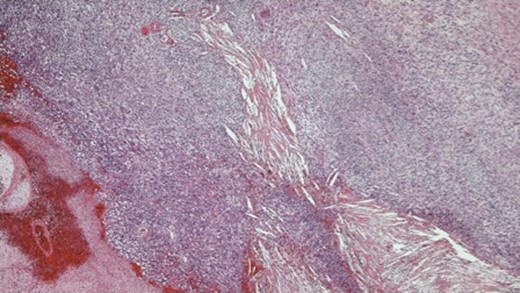

The histopathology demonstrated that the breast was partially replaced by a partly cystic and partly solid necrotic lesion. The cystic cavity contained blood clots. A microscopic examination showed an atypical undifferentiated spindle cell lesion with a fascicular architecture, pleomorphism and marked mitotic activity with areas of ulceration and necrosis (Figs 1 and 2). The initial set of immunostains performed showed that tumour cells were negative for cytokeratins (Fig. 3), S100 and LCA. The tumour cells showed diffuse and strong vimentin positivity (Fig. 4). Further immunocytochemical labelling showed weak expression of CD99, patchy strong expression of CD10 and patchy weak expression of smooth muscle actin. Cytokeratins (CAM 5.2) and EMA were expressed and there was no tumour-specific expression of CD34, desmin or myogenin. Fluorescent In-situ hybridization analysis failed to demonstrate evidence of a t(x:18) translocation using the LYS-SYT break apart probe. The diagnosis of a Grade 3 undifferentiated spindle cell sarcoma was made and although the tumour was reported to have a clear resection margin (5 mm) in most areas, the presence of necrosis and granulation tissue reaching the deep margin made the status of the margin uncertain.

Photomicrograph ×4 H&E; spindle cell tumour with areas of haemorrhage and necrosis.